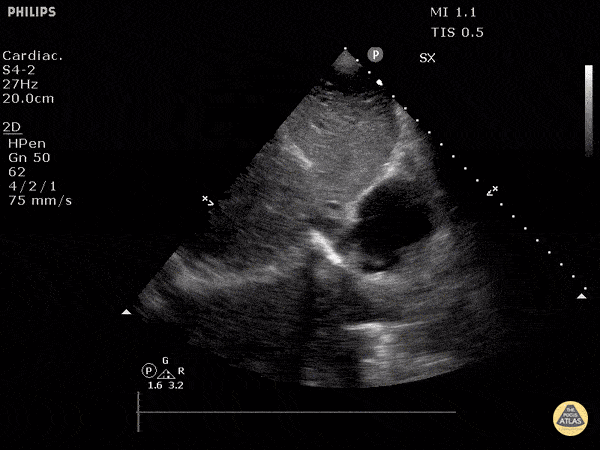

Normal Cardiac Anatomy - Inferior Vena Cava Emptyting into Right Atrium

Normal IVC seen in longitudinal view, emptying into the right atrium. Justin Bowra MBBS, FACEM, CCPU Emergency Physician, RNSH et al.